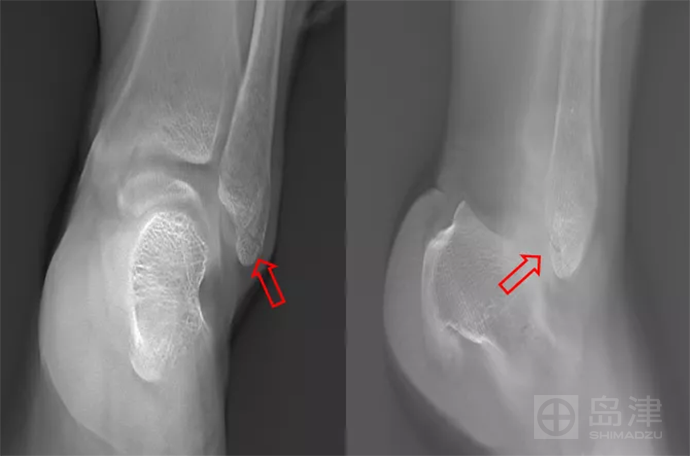

45岁 女性 左踝扭伤

左踝正侧位X线片无明显骨折线,骨折间接征象:软组织肿胀亦不明显。

查体:局部压痛明显。

DTS发现骨折,与 CT对比结果一致。

隐匿性骨折 DR无法发现

左外踝隐匿性骨折

DTS可发现平片无法发现的骨折

图像来源:西安市第九医院